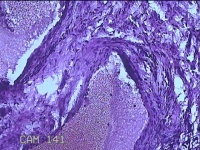

肛门肿物

性别

女

年龄

41岁

临床诊断

混合痔

一般病史

发现肛门肿物突出伴大便带血2年。

标本名称

大体所见

灰白暗红色皮肤肿物1.5x1.3x0.3cm一个,表面糜烂,切面灰白粉红色,质软。